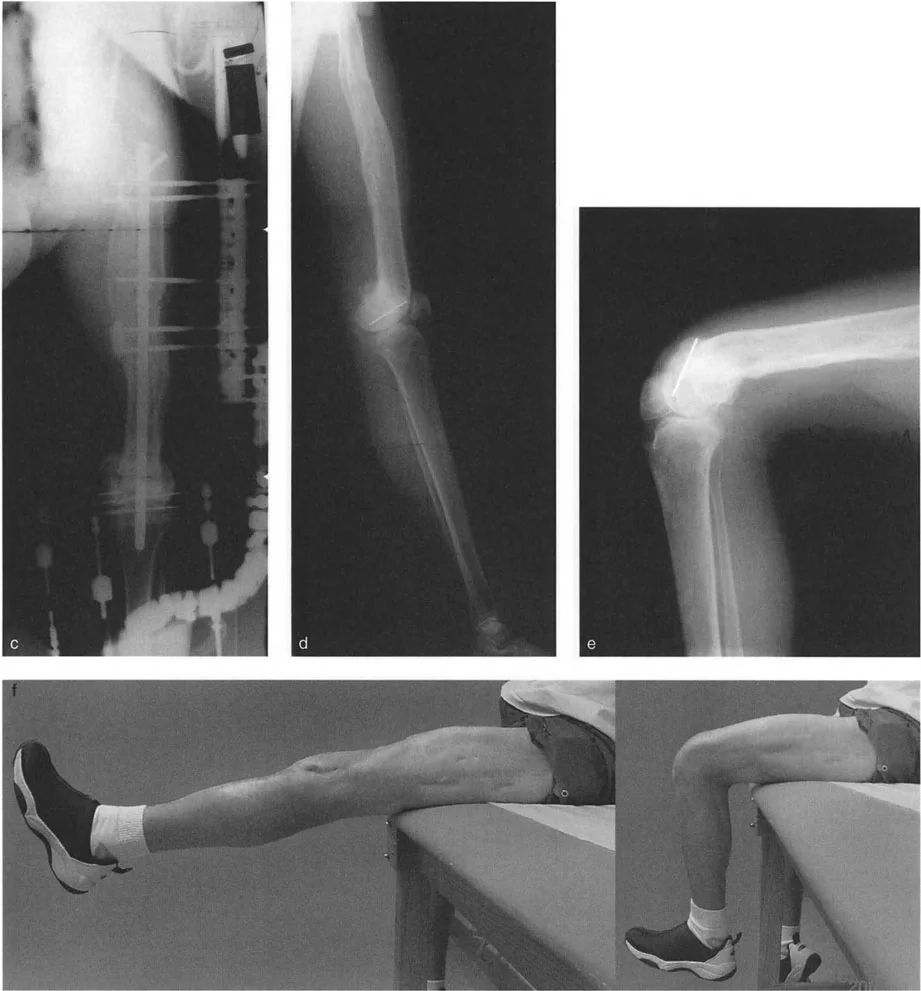

التقوس الخلفي بعد العلاج الإشعاعي

يمكن أن يسبب العلاج الإشعاعي في مرحلة الطفولة (الذي يستخدم عادة للأورام اللحمية، أو ساركوما إيوينغ، أو غيرها من الأورام الخبيثة لدى الأطفال) توقفاً مدمراً وغير متماثل في صفيحة النمو. نظراً لأن الجانب الأمامي من صفيحة النمو الظنبوبية القريبة أقرب إلى الجلد، فإنه غالباً ما يتلقى جرعة أعلى من الإشعاع وينغلق مبكراً، بينما تستمر صفيحة النمو الخلفية في النمو. يدفع هذا عظم الظنبوب إلى تقوس خلفي عميق.

في هؤلاء المرضى، غالباً ما يتم إدخال وتر الرضفة بشكل غير طبيعي بالقرب من خط المفصل، مصحوباً بخلع جزئي حقيقي خلفي للركبة.

يتضمن التصحيح قطع عظمي دقيق على شكل إسفين فتح فوق الحدبة الظنبوبية، جنباً إلى جنب مع نقل الظنبوب للأسفل باستخدام إطار دائري. يحقق هذا تقليلاً غير مباشر للظنبوب، ويحل تماماً خلع الركبة الجزئي والتقوس الخلفي مع الحفاظ على ارتفاع الرضفة الطبيعي.

تُوضح الصورة كيفية تصحيح التقوس الخلفي الناتج عن العلاج الإشعاعي باستخدام جهاز إليزاروف، مما يحقق محاذاة طبيعية للركبة.